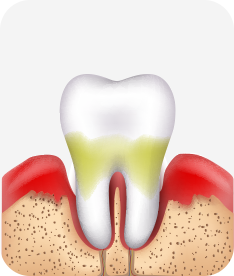

치주염 (중기~말기)

주기적으로 잇몸이 붓고 피가 나며, 욱씬하거나 우리한 통증이 나타남.

치주치료 및 정도에 따라 치주수술(잇몸수술)이 필요함. 향후 관리 정도에 따라 3~6개월 간격으로 내원하여 유지치료를 시행하여야 함.